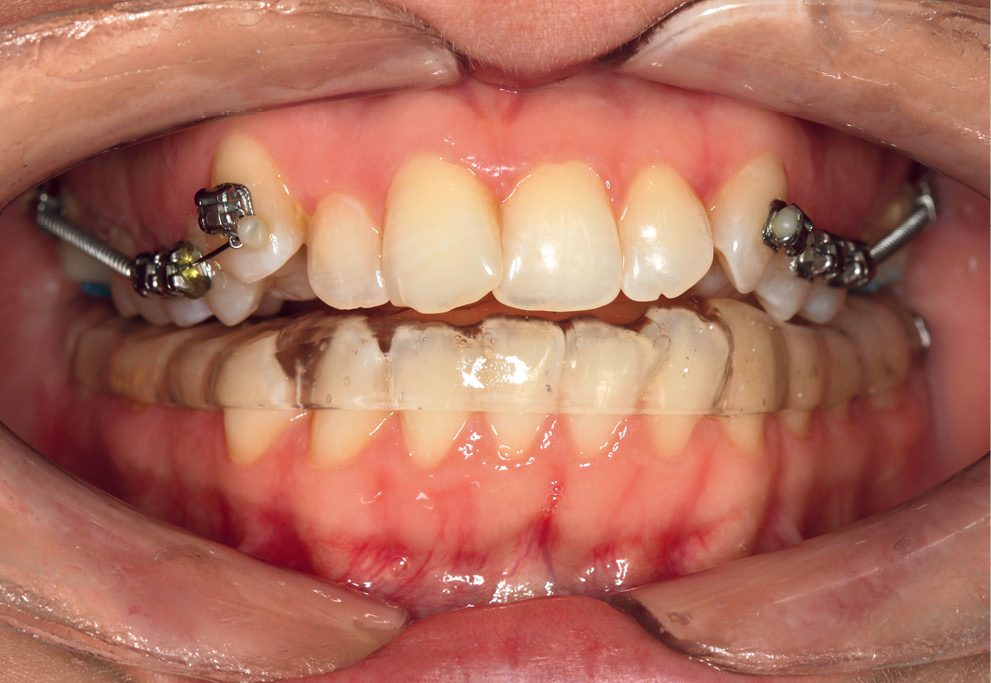

Все пациенты проходили курс консервативного лечения с использованием дистракционной лечебно-диагностической каппы на нижней челюсти в течение 3-4 мес (рис. 2), после чего проводилась повторная диагностика, по результатам которой принималось решение о проведении хирургического вмешательства на ВНЧС при наличии показаний.

Рис. 2. Консервативное лечение с использованием дистракционной лечебно-диагностической каппы

Примечание. Лечебно-диагностическая дистракционно-протрузионная каппа на нижней челюсти: этап коррекции.